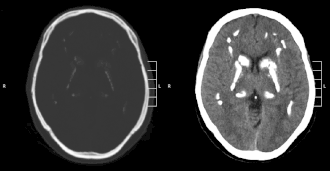

Идиопатическая кальцификация базальных ганглиев 1 (синдром Фара) характеризуется накоплением кальция в различных областях мозга, преимущественно в базальных ганглиях. Деградация функций нервной системы у пациентов с синдромом становится заметной в возрасте от 30 до 50 лет, но может появиться в детстве или в более позднем возрасте.